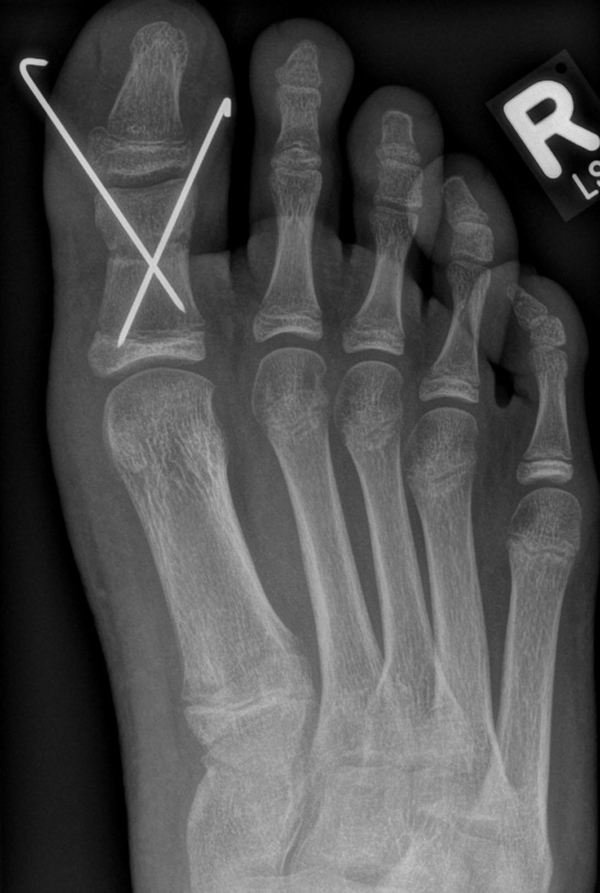

Werden komplette Osteotomien an den Zehen durchgeführt, fädeln wir die Osteotomien mit einem 1.2 oder 1.4 mm Kirschner-Draht auf, damit die einzelnen Fragmente nicht verkippen (Abb. 22).

Abb. 22 a-d: Präoperative Klauenzehen beim Jugendlichen in zwei Ansichten (a-b) und postoperative Auffädelung mit Kirschner-Drähten linker und rechter Fuß (c-d).

Nach unserer Erfahrung können komplette Osteotomien nicht so gut in einem Tapeverband stabil gehalten werden. Im Fall von Derotationen kombinieren wir einen Draht mit externen Tapezügeln, um das Ergebnis zu sichern. Die Drähte werden 2-3 Wochen belassen und anschließend in der Sprechstunde gezogen. Anschließend wird die Zehe noch 2 weitere Wochen mit Tape gezügelt (Abb. 23).